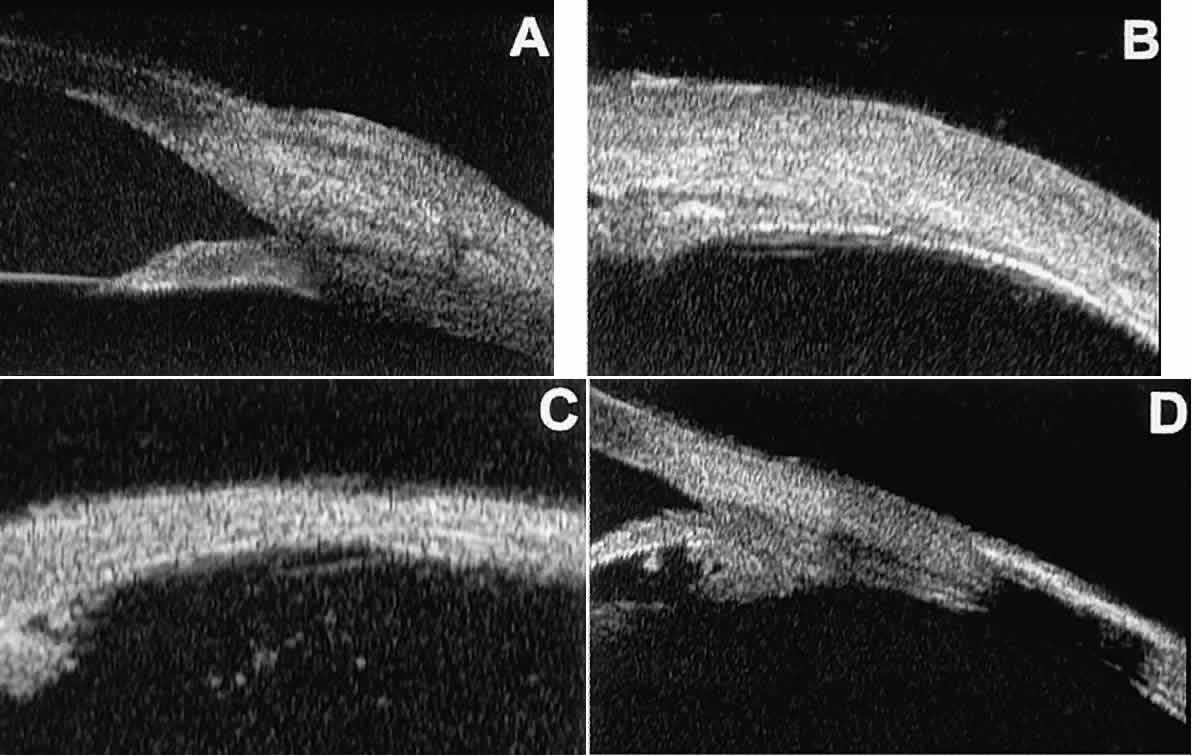

In open-angle glaucoma, UBM can be used to measure the anterior chamber angle in degrees, to assess the configuration of the peripheral iris, and to evaluate the trabecular meshwork (Fig. 9).2,4 The angle configuration can be graded and compared with gonioscopic findings. In certain patients with open-angle glaucoma, UBM can provide information that may be of some diagnostic value (Fig. 10). For example, in pigment dispersion syndrome (see Fig. 10A),6 UBM typically reveals posterior bowing of the peripheral iris (“q” configuration of peripheral iris by Spaeth classification5). In plateau iris syndrome (see Fig. 10B),7 UBM usually reveals abnormally steep anterior angulation of the peripheral iris (“s”configuration of peripheral iris by Spaeth classification5), insertion of the iris from the anterior ciliary body, and retroiridic projection of the ciliary processes. In eyes with peripheral anterior synechiae (see Fig. 10C and D), UBM can reveal the extent of iridocorneal adhesion even if the cornea is hazy or opaque.

Fig. 9. Angle configuration in eyes with open-angle glaucoma. A. Wide open angle with flat iris plane (D40r configuration by Spaeth gonioscopic grading system). B. Moderately wide angle with anteriorly bowed iris plane (C30r by Spaeth gonioscopic grading system).

Fig. 10. UBM features of special glaucoma cases. A. Pigment dispersion syndrome with posterior bowing of peripheral iris (“q” configuration by Spaeth gonioscopic grading system). B. Plateau iris syndrome with origin of iris from anterior surface of ciliary processes behind peripheral iris, slitlike narrowing of peripheral angle, and abrupt transition from steep peripheral iris to flat iris midzone. C. Broad peripheral anterior synechia with posterior bowing of nonadherent iris. D. Peripheral anterior synechia with aqueous-filled slit between site of iridocorneal adhesion and iris root after cataract extraction with implantation of posterior-chamber IOL.